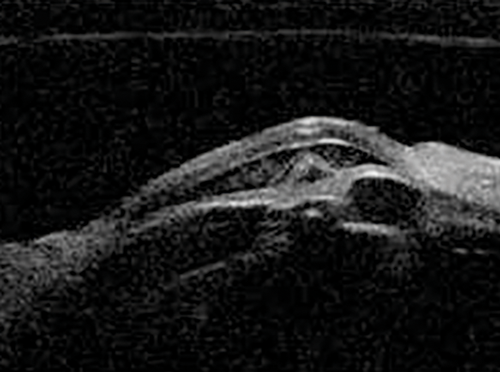

Figure 12: Blunt trauma causing cyclodialysis cleft. A direct communication between

the supra-ciliary space and anterior chamber can be visualised.

Cyclodialysis clefts

Cyclodialysis clefts can be iatrogenic or more commonly secondary to contusion injuries. Defined as a disinsertion of the ciliary body from the scleral spur, the injury allows access to the suprachoroidal space resulting in hypotony. Visualisation of the supraciliary fluid and the connection from the anterior chamber to the supraciliary space confirms the diagnosis of a cyclodialysis cleft (Figure 12). Direct gonioscopy once the eye is filled with viscoelastic is the definitive way of determining the location and extent of the cleft, principally because the iris will otherwise obscure the angle. UBM is useful in this scenario as it provides a way of knowing the location and extent of the cleft without physically entering the anterior chamber.